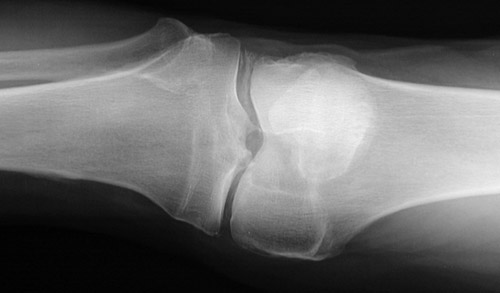

![]() | This series of knee radiographs reveals extensive chondrocalcinosis involving the menisci and articular cartilage. Note particularly the chondrocalcinosis of the meniscus above. Chondrocalcinosis is a condition related most to aging with calcium pyrophosphate dihydrate (CPPD) crystal deposition. The relationship to osteoarthritis is not clear, but CPPD disease can contribute to osteoarthritic changes, which are also present in these radiographic views. In the case shown here, bone density is not decreased. |